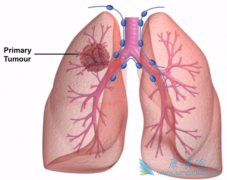

PACIFIC 研究是首个探索 免疫检查点抑制剂 序贯用于Ⅲ期NSCLC患者的全球范围的大型随机、双盲、前瞻性Ⅲ期临床研究。PACIFIC研究之所以能够大获成功,主要是基于它在研究设计上非常合理,在临床前和前期的临床研究中已有结果显示,放疗可以对免疫治疗起 ...

据报道,EGFR 突变的腺癌TKI(酪氨酸激酶)治疗耐药后有转换成小细胞肺癌的可能。在初始病理诊断中可能存在两种癌细胞,但仅诊断出来非小细胞肺癌。然而,小编查阅文献时发现有研究报道,用PD-1抑制剂治疗期间也有可能将晚期 非小细胞肺癌 (NSCLC)转化 ...

局部晚期(III期) 非小细胞肺癌 (NSCLC)约占NSCLC总数的1/3,这一期肺癌包括IIIa和IIIb两个亚组,大部分患者是不能接受手术治疗的,目前的标准治疗是同期放化疗,其5年生存率一般在10%~15%左右,治疗效果一直不令人满意。在传统手段无法进一步改善III ...

11月2号,辉瑞公司宣布,美国FDA批准了其公司的第三代ALK-TKI药物Lorlatinib(中文名: 劳拉替尼 )上市,用于治疗ALK阳性的转移性非小细胞肺癌(NSCLC)患者。可使用Lorlatinib的这类ALK阳性转移性NSCLC患者的特征:(1)使用克唑替尼后或在至少使用一 ...

阿来替尼( 安圣莎 )在中国迅速获批上市,用于ALK阳性非小细胞肺癌,我们知道,对于ALK阳性肺癌患者靶向药的选择比较多,比如我们熟知的克唑替尼,很多患者的用药顺序是先用克唑替尼,等耐药之后再用阿来替尼,我们知道阿来替尼的疗效数据非常惊人,效 ...